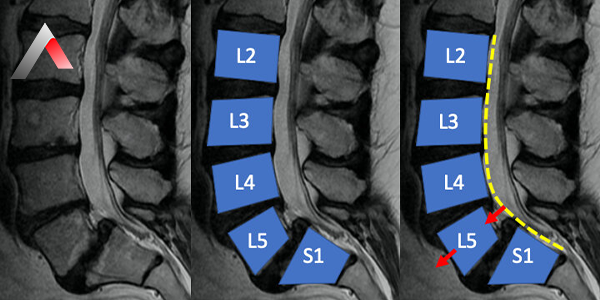

Spondilolistezis, omurganın bir bölümünde bir omurun altındaki omurun üzerine kayması durumudur. Bu kayma, omurganın stabilitesini bozarak sinirlere baskı yapabilir ve çeşitli semptomlara yol açabilir. Spondilolistezis en sık bel bölgesinde (lomber spondilolistezis) görülür, ancak boyun (servikal spondilolistezis) ve sırt (torakal spondilolistezis) bölgelerinde de görülebilir.

Spondilolistezis Dereceleri

Spondilolistezis, kaymanın şiddetine göre derecelendirilir:

• Derece 1: %25'e kadar kayma

• Derece 2: %25-50 arası kayma

• Derece 3: %50-75 arası kayma

• Derece 4: %75'ten fazla kayma